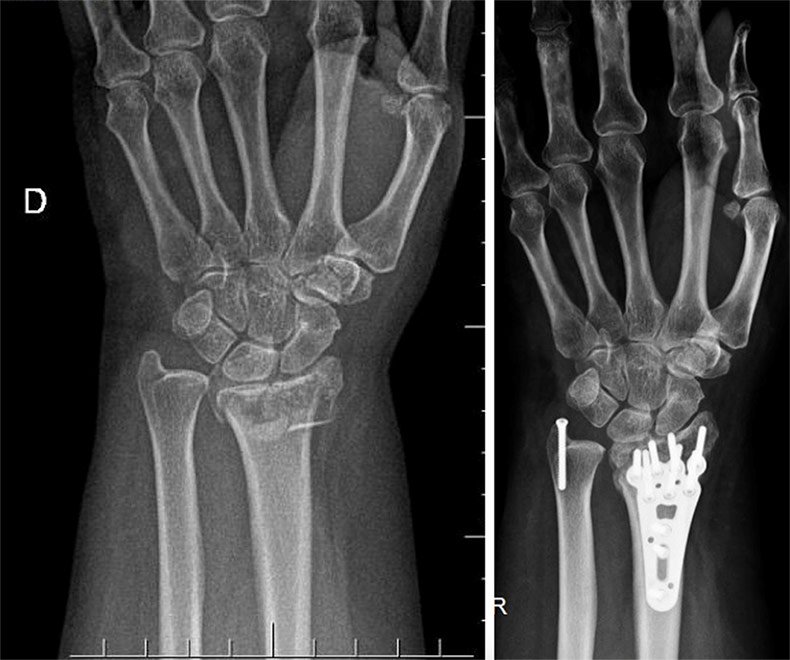

Epidemiology. Radius and ulnar shaft fractures are common fracture patterns and can be a result of either direct or indirect trauma. They are also known as " both bone forearm fractures " 1,2,4. These fractures have a bimodal age distribution and typically occur in young males aged between 10-20 years or females over the age of 60 years.. All the football fixtures, latest results & live scores for all leagues and competitions on BBC Sport, including the Premier League, Championship, Scottish Premiership & more.